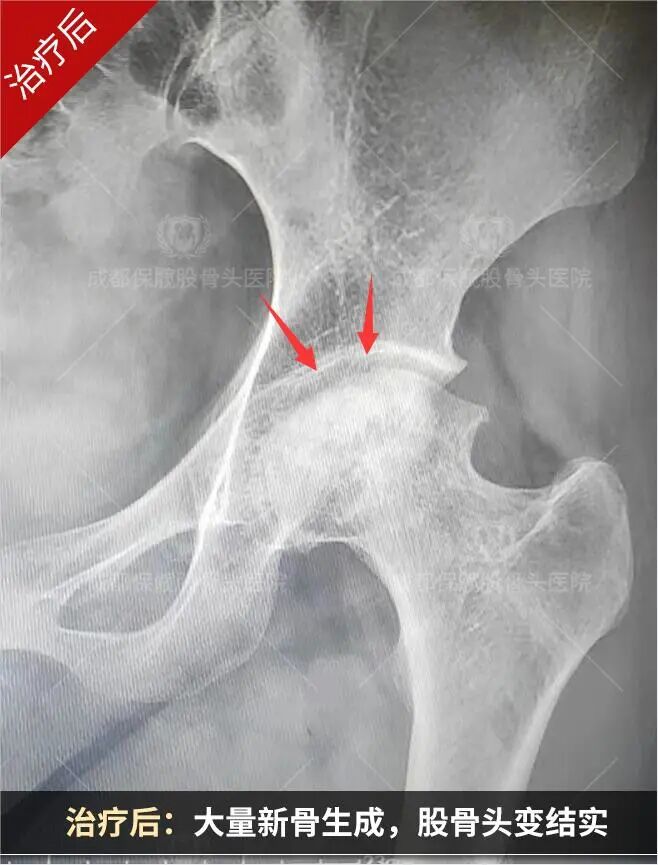

谁说股骨头塌陷了就只能换关节